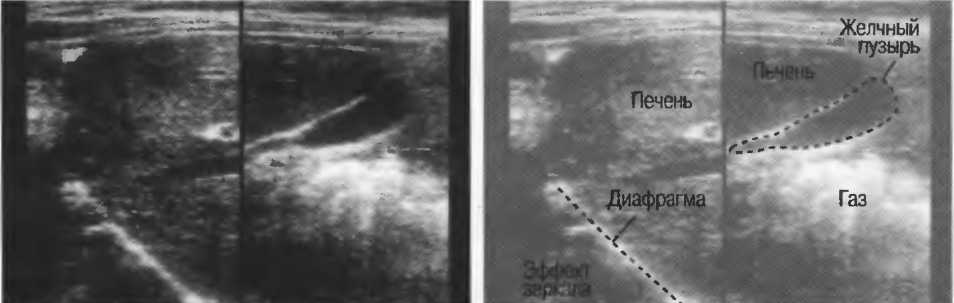

Реверберации имеют место при прохождении ультразвукового луча от одного вида ткани к другому при резко выраженном различии акустического сопротивления этих тканей, например от кишечного газа к печени или ребрам: реверберации могут экранировать ткани, лежащие за газом (рис. 20а).

Рис.20а. Артефакты, связанные с газом. Слева: над диафрагмой повторяется изображение печени из-за наличия газа в легких. Справа: характерные артефакты при наличии газа в кишечнике за желчным пузырем могут быть интерпретированы как реальные структуры в области тела желчного пузыря.